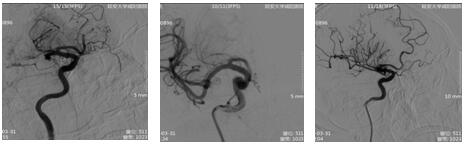

17:21 DSA示:右側(cè)大腦中動(dòng)脈、前動(dòng)脈閉塞。與患者家屬談話,簽字后立即行中動(dòng)脈、前動(dòng)脈取栓術(shù)。

18:55 術(shù)后患者神經(jīng)功能及肢體功能逐漸恢復(fù),意識(shí)轉(zhuǎn)清,上肢肌力4級(jí),下肢肌力3級(jí)。卒中中心又成功救治一名危重患者。這是一場(chǎng)與時(shí)間的賽跑,更是一場(chǎng)與死神的搏斗。